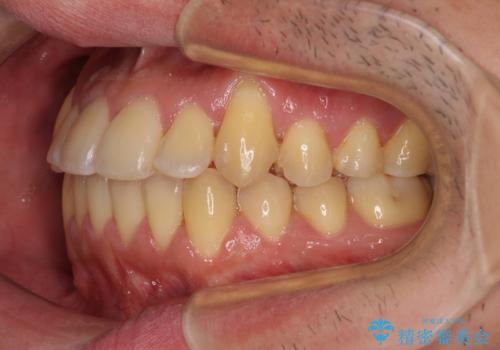

八重歯とクロスバイト 目立たないワイヤー装置で矯正治療

- 八重歯と前歯のクロスバイトを改善したいとのことで来院された患者様です。

マウスピース矯正での自己管理には自信がないとのことで、ワイヤー装置による矯正治療を行うこととしました。

デコボコが解消されると歯列が拡大される方向に動くため、出っ歯のような仕上がりとなることがあります。舌の突出癖を改善するトレーニングをしっかりと行っていただくことで、突出を抑制することができます。